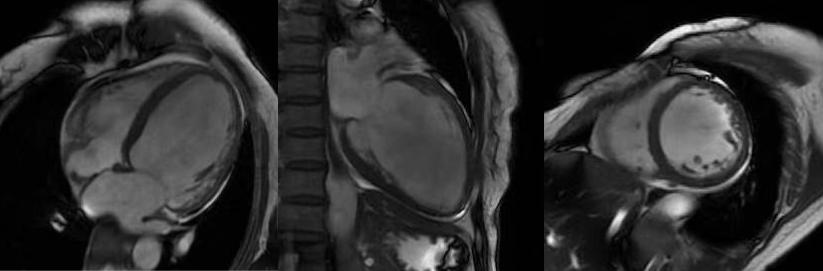

心臟磁共振被稱為心臟“一站式”檢查,通過多參數(shù)成像能夠?qū)π呐K的結構、功能、室壁運動、心臟瓣膜、心肌灌注和活性進行“一站式”評估。主要通過電影序列(短軸、兩腔心、四腔心、三腔心)、T2WI序列、首過灌注序列以及延遲強化序列對心臟進行綜合成像。

擴張型心肌病

肥厚型心肌病,舒張末期心尖形似“黑桃A征”